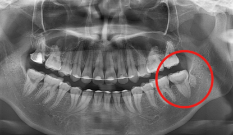

Case 07. 매복된 치아 & 쓰러진 어금니

영구치가 잘못된 방향으로 나거나 제때 올라오지 못하면 턱뼈 속에 갇히는 ‘매복 치아’가 생기며, 교정 치료로 올바른 방향으로 유도·견인해 정상교합 관계를 회복합니다.

어금니가 빠진 뒤 오랫동안 방치하면 인접 치아가 쓰러지고 맞물리던 치아가 내려오는데, 이 경우 쓰러진 어금니를 세우고 위치를 바로잡는 교정 치료로 씹는 힘과 치열의 균형을 되찾을 수 있습니다.

교정 치료 Before & After

• 매복된 치아

Before

After

• 쓰러진 어금니